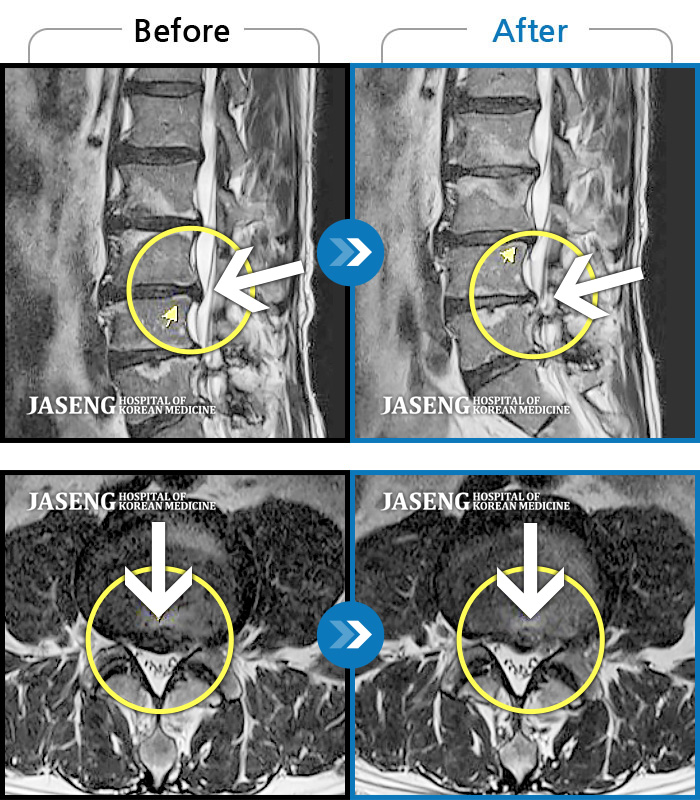

허리디스크

광주 · 이일석 원장

허리부터 골반이 묵직하고 뻐근한 통증, 우측 허벅지까지 이어지는 저림 증상으로 내원하셨습니다.

촬영시기

2025.01.20 ~ 2025.10.25